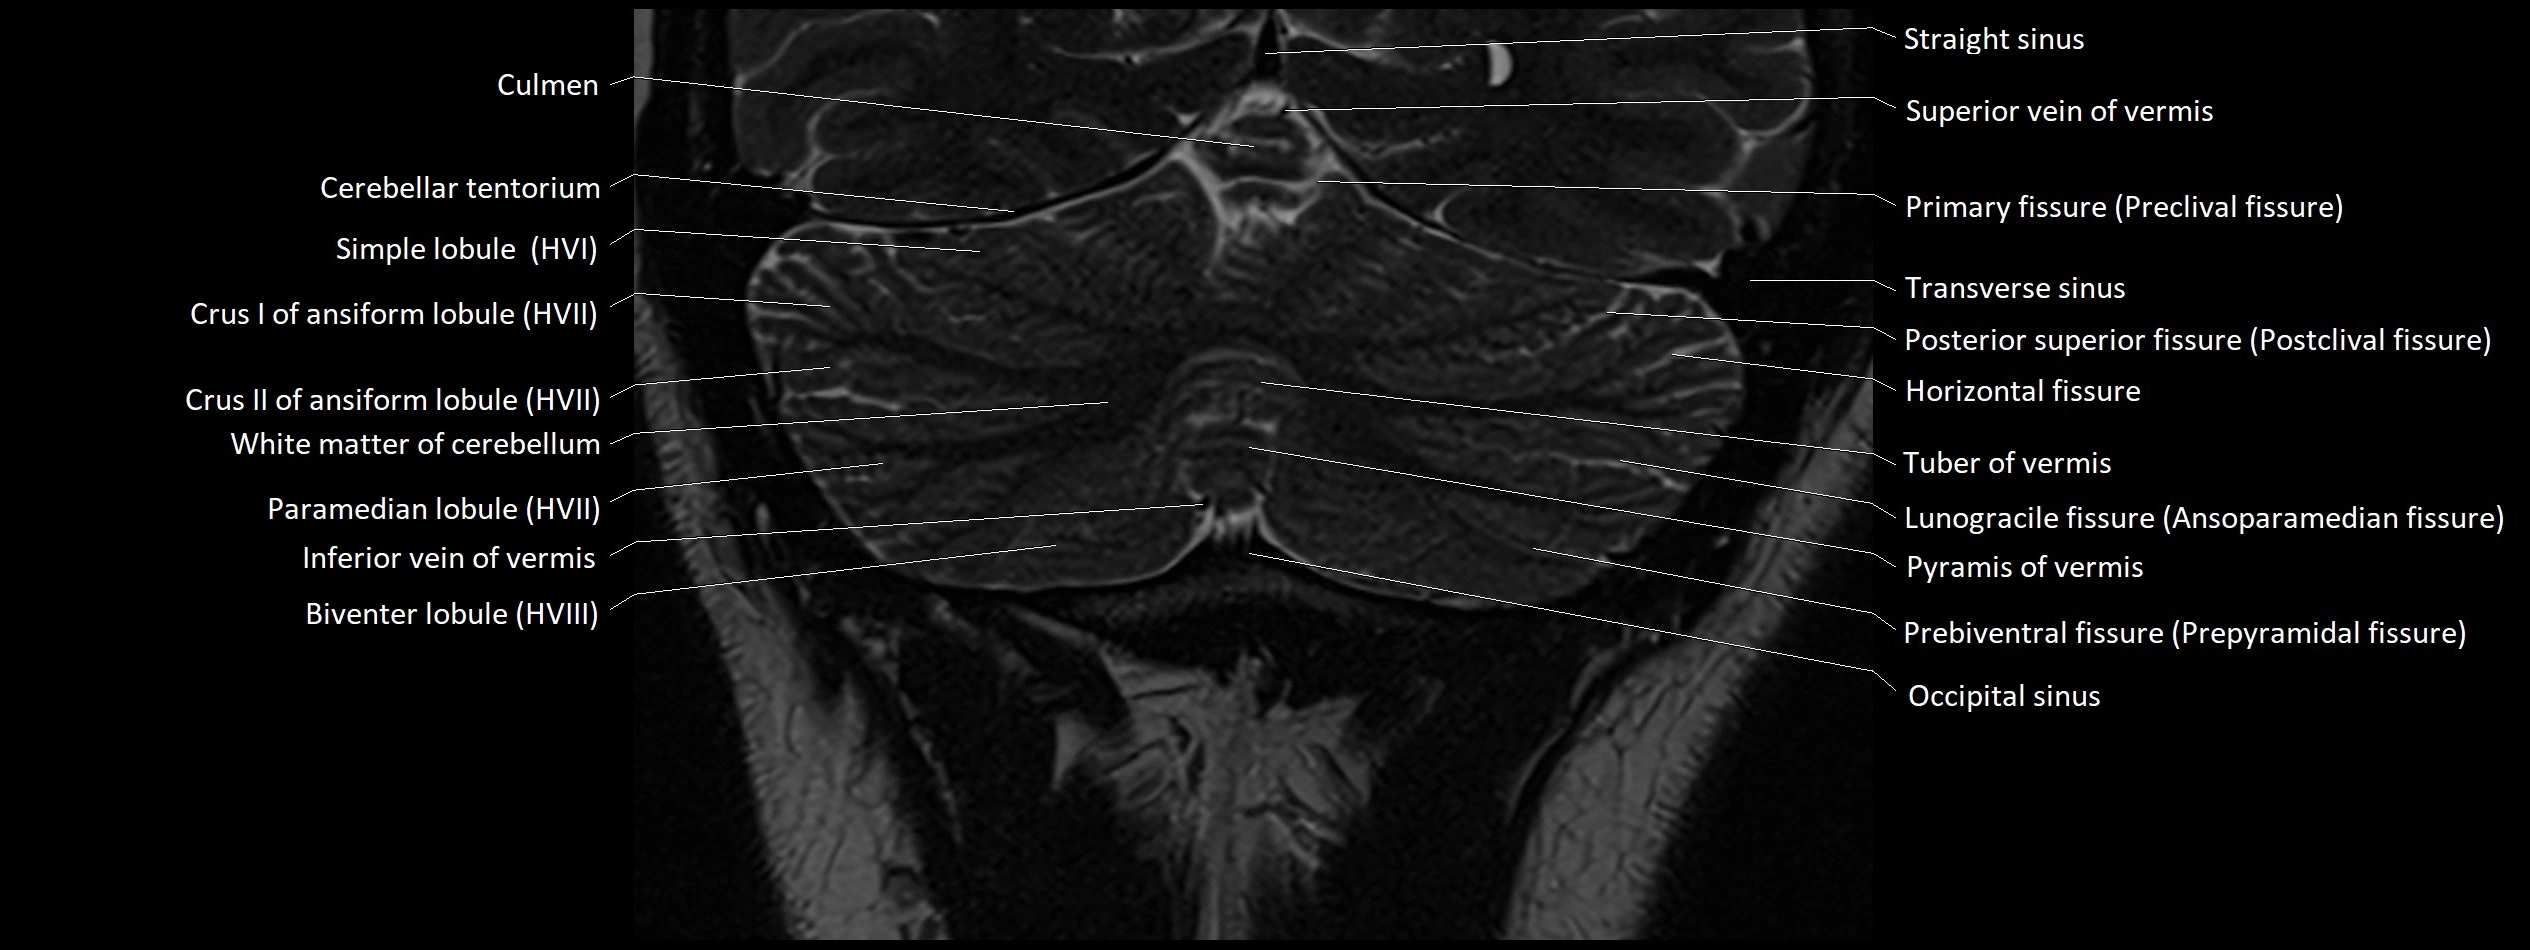

MRI images